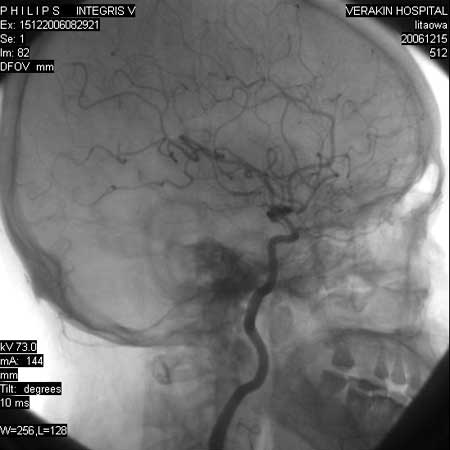

标题: DSA0063:颈内动脉血管造影

女,60岁,行全脑血管造影,图片较多,选了左颈内动脉造影100幅图中的10幅图片,请包涵。

支持后交通动脉起始部动脉瘤。

后交通动脉瘤.

另外:大家讨论的\"动脉瘤\"实际是血管分支重叠影像,本帖单侧颈内动脉仅见轻度动脉硬化性狭窄..参考旋转dsa请连接:http://www.sdhct.com.cn/radinet/read.php?tid=19818